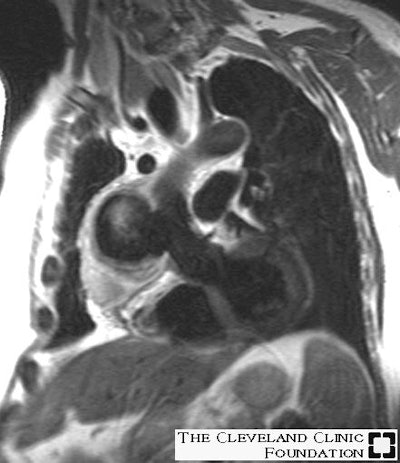

Infectious Aortic Pseudoaneurysm:

Below are images of a pseudoaneurysm at the distal anastamosis of an ascending aortic homograft that occurred secondary to infection. Both images were obtained in a double oblique coronal projection. The first image is a fast spin-echo T2-weighted sequence showing the large pseudoaneurysm that contains a mild amount of thrombus along the periphery, while the second image is a cine gradient-echo demonstrating the wide (3 cm) communication between the pseudoaneurysm and the ascending aorta.